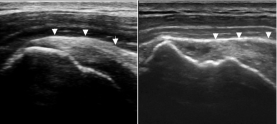

-Refer to the figure. If you compare the longitudinal ultrasound scan of the supraspinatus muscle and tendon (arrowheads) on the right with the normal supraspinatus on the left, what are your findings?

A) Thickened supraspinatus tendon

B) Swollen subacromial bursa

C) Cortical irregularities and a partial tear

D) Hyperechoic focus in the distal tendon